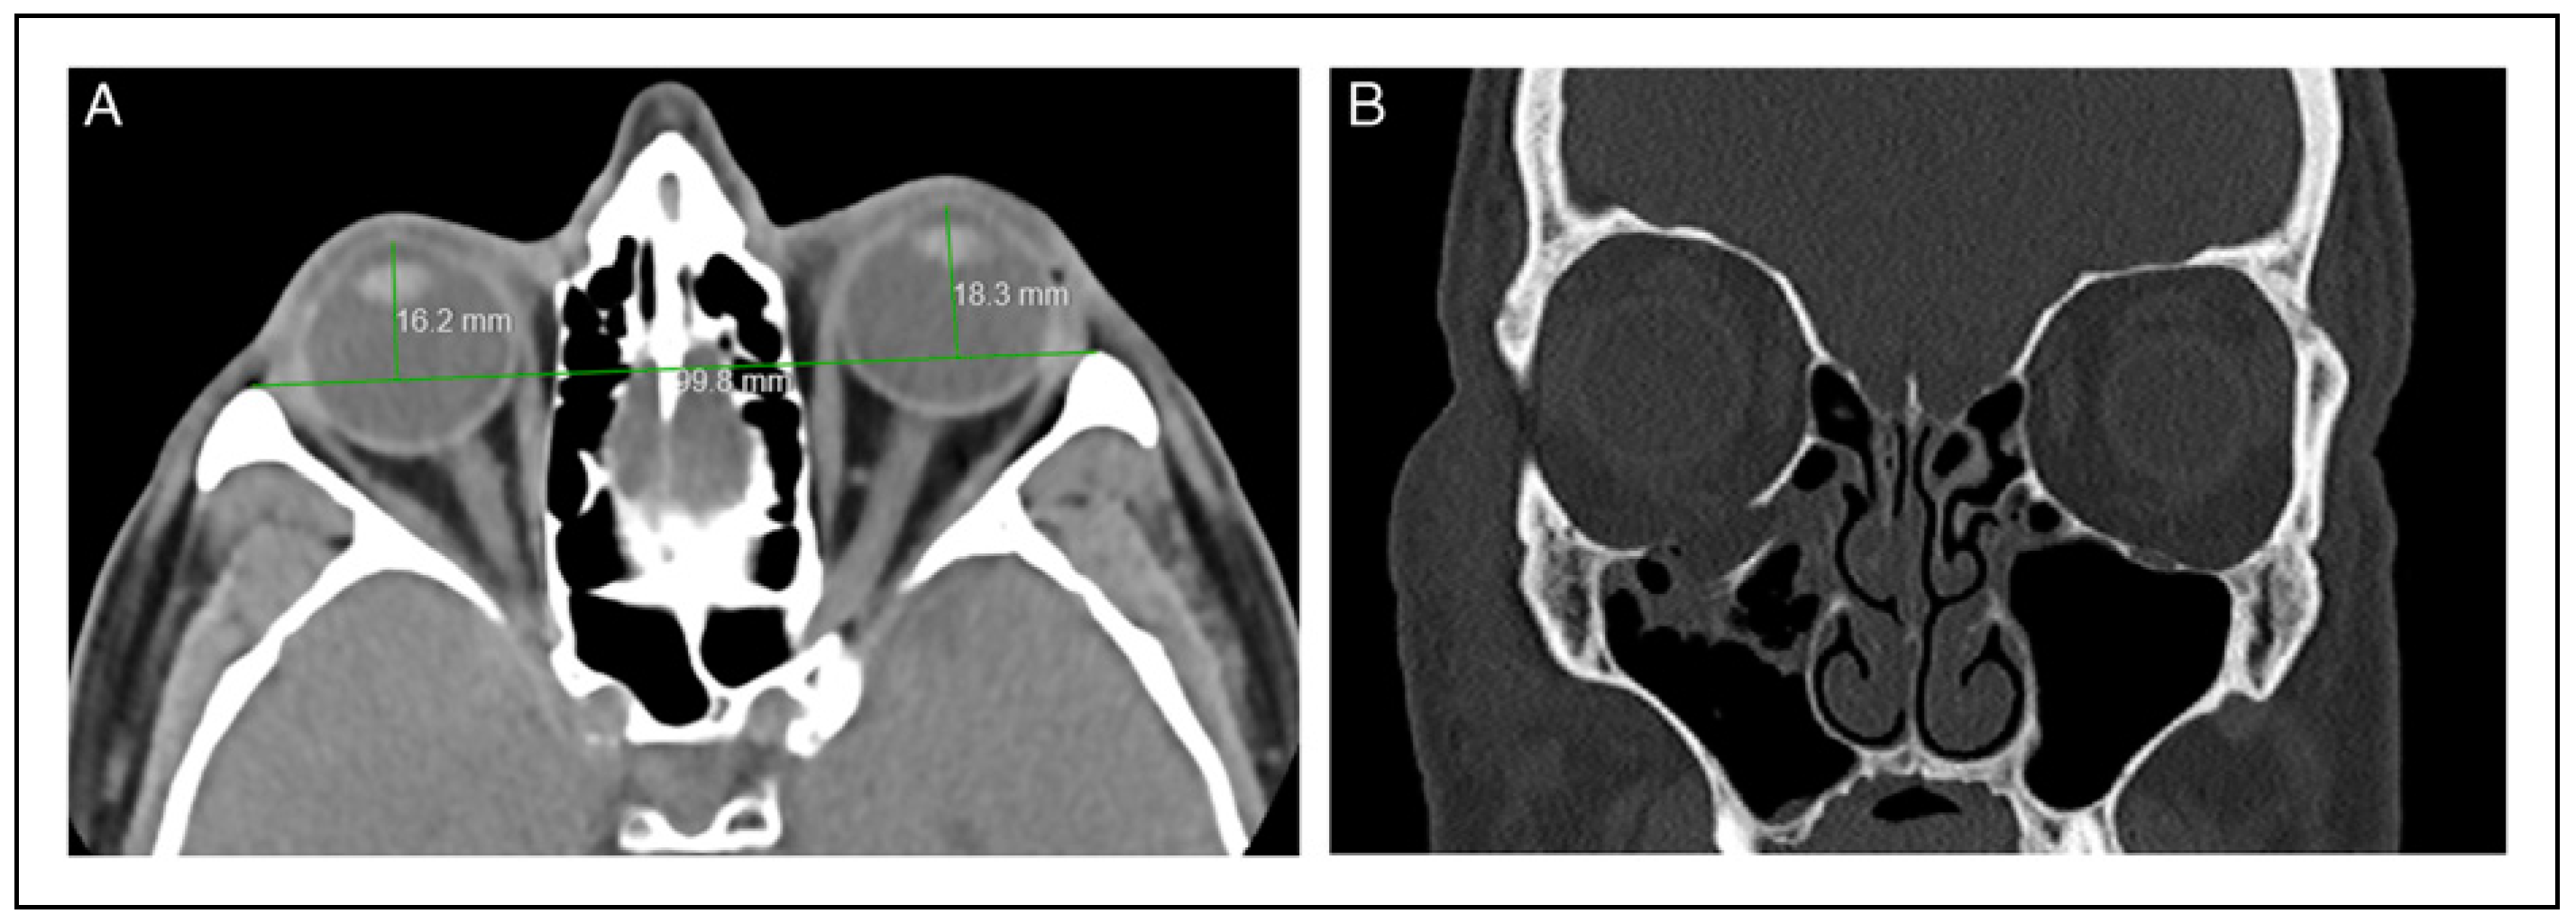

An additional factor that is a predictor of whether a patient will eventually develop enophthalmos following an orbital floor fracture is based on the shape of the inferior rectus muscle following an orbital floor fracture. Chiasson and Matic found that if the inferior rectus, as viewed on the coronal cuts of the CT, changes from an elliptical shape to a more rounded shape the patients are more likely to develop enophthalmos when the periorbital edema subsides [31].

Figure 6 is a photo of a patient who is a pilot who was involved in a plane crash with a significant right orbital floor fracture. He was followed by the senior surgeon with Naugle exophthalmetric measurements for 2 years, and indeed developed 3 mm of enophthalmos on his right side. His CT views of his orbit (Figure 7A,B) demonstrate a significant orbital floor fracture and a significant rounding of the inferior rectus muscle compared to the relatively flat appearance of the contralateral muscle. He never had a surgical correction and never developed diplopia, which would be a significant handicap to him, or any other patient if caused by a post-surgical procedure. His 2-year post-trauma photos were presented at an advanced AOCMF Orbit Course where the participants, with a specific interest in orbital trauma were asked which side the defect was on [32]. The choices offered were the “right side”, the “left side”, or the participant “did not know” the side of the enophthalmos. Eight percent of the participants chose the correct side, 48% chose the wrong side, and 44% did not know. The patient who now is out of state was contacted 14 years post-trauma and he and his family still do not notice a difference between the normal side and the side that sustained his orbital trauma. The critical question that needs to be asked is the following. If a patient has a measurable enophthalmos of ≥3 mm, but has no diplopia, no other symptoms, and most friends and family members do not notice the deficit, are the risks and costs of a surgical correction justified?

Figure 7. (A) Coronal CT of the orbit of the pilot demonstrating a large right orbital floor fracture with a significant rounding of the inferior rectus muscle. (B) Oblique para-sagittal CT of the orbit of the pilot demonstrating a large right orbital floor fracture.